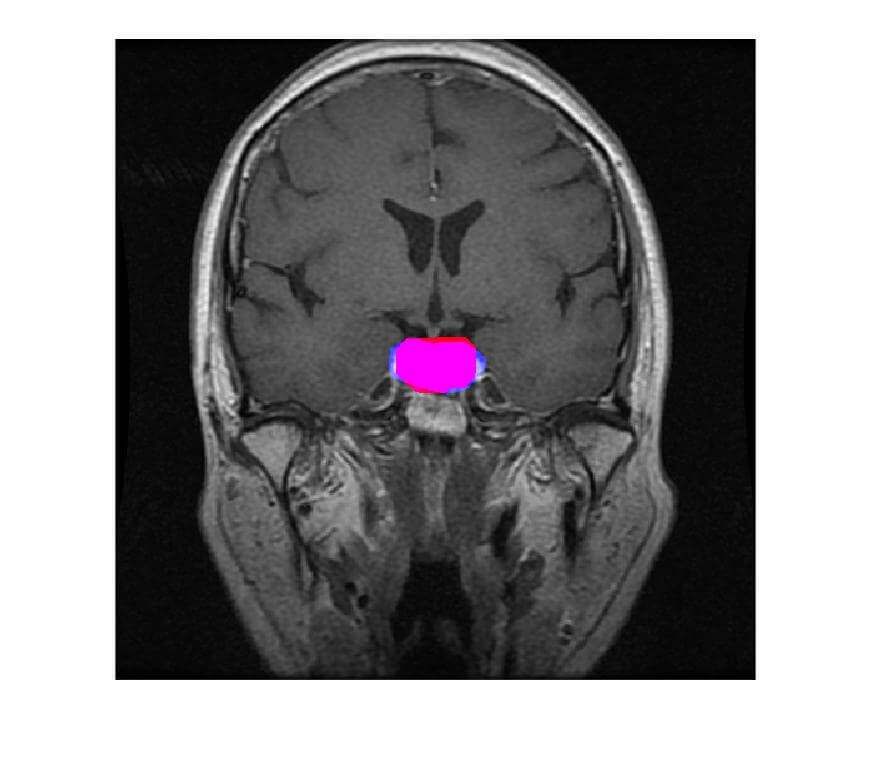

- The extracted tumor will be highlighted in red color and Blue color is the true tumor.